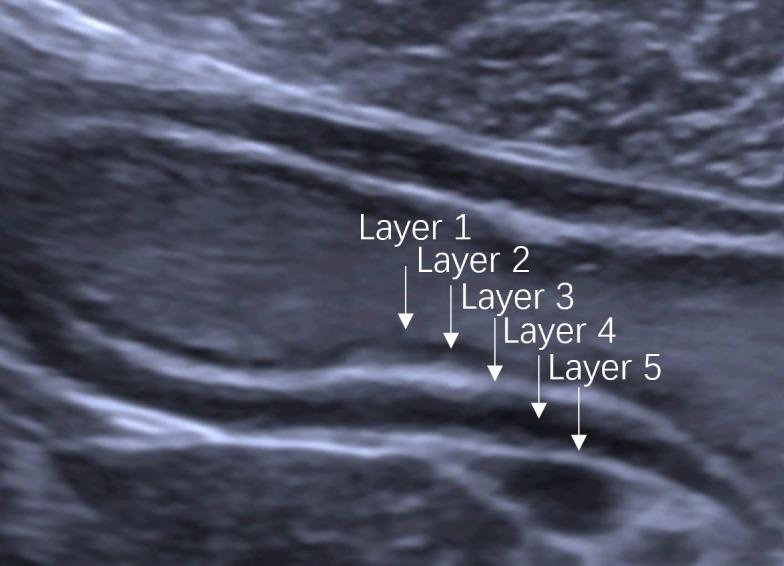

This single prospective study enrolled patients with GC confirmed by preoperative gastroscopy from July 2021 to March 2023. Patients underwent DCEUS, including ultrasonography (US) and intravenous contrast-enhanced ultrasonography (CEUS), and MDCT examinations for the assessment of preoperative T staging. Features of GC were identified on DCEUS and criteria developed to evaluate T staging according to the 8 edition of AJCC cancer staging manual. The diagnostic performance of DCEUS was evaluated by comparing it with that of MDCT and surgical-pathological findings were considered as the gold standard.